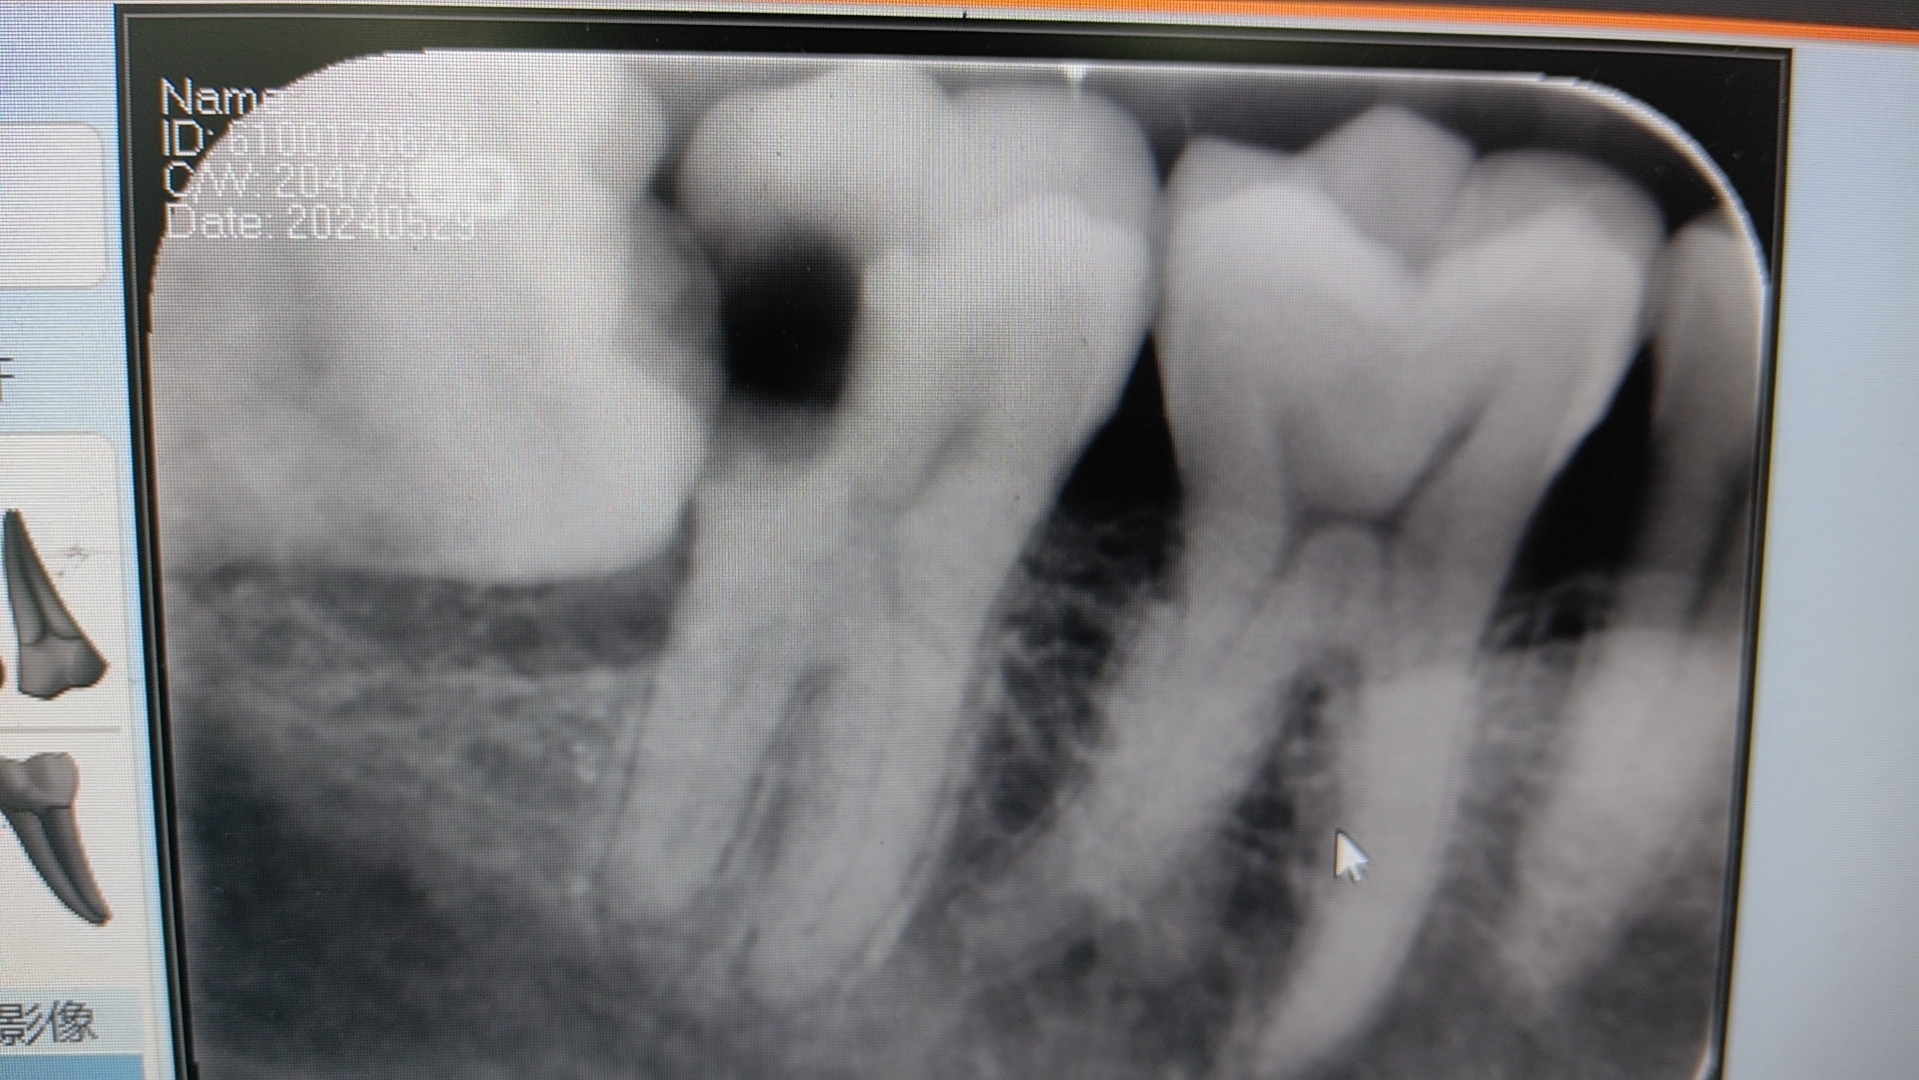

口腔內(nèi)需要拔除的牙有最多見的有這幾種1、慢性牙周病。2、無法保存的殘冠殘根。3、智齒,下頜智齒包括橫位的和正位的,把第二磨牙頂壞的,對頜牙缺失后,伸長的、齲壞的智齒。拔牙前需要做的準(zhǔn)備:1、是否有心血管疾病,心臟病血壓高拔牙需要慎重,一般沒有心電監(jiān)護的醫(yī)院不能給嚴(yán)重心臟病患者拔牙,如房顫,冠心病等,高血壓患者也是要慎重,高壓高于130,低壓低于70的患者都要謹(jǐn)慎,口服阿司匹林,或華法林等增強血溶性的藥物不能拔牙,另外,打了抗骨質(zhì)疏松的針劑,明確規(guī)定,不能拔牙。牙疼痛急性期是不能拔牙的,需要先口服抗生素消炎后方可拔牙。2、關(guān)于拔智齒,拔前需要拍片,全口片或者CBCT,簽手術(shù)同意書,不能空腹拔牙,橫位和多根的智齒需要分牙及分根后拔除,并且需要術(shù)后縫合。拔牙后會有張口受限,疼痛,腫脹等術(shù)后反應(yīng),這些是正常的,如果拔后出血不止,下唇麻木,或者有上頜竇底損傷,如鼻腔嗆水,口內(nèi)漏氣等,則需要找主診大夫復(fù)查。